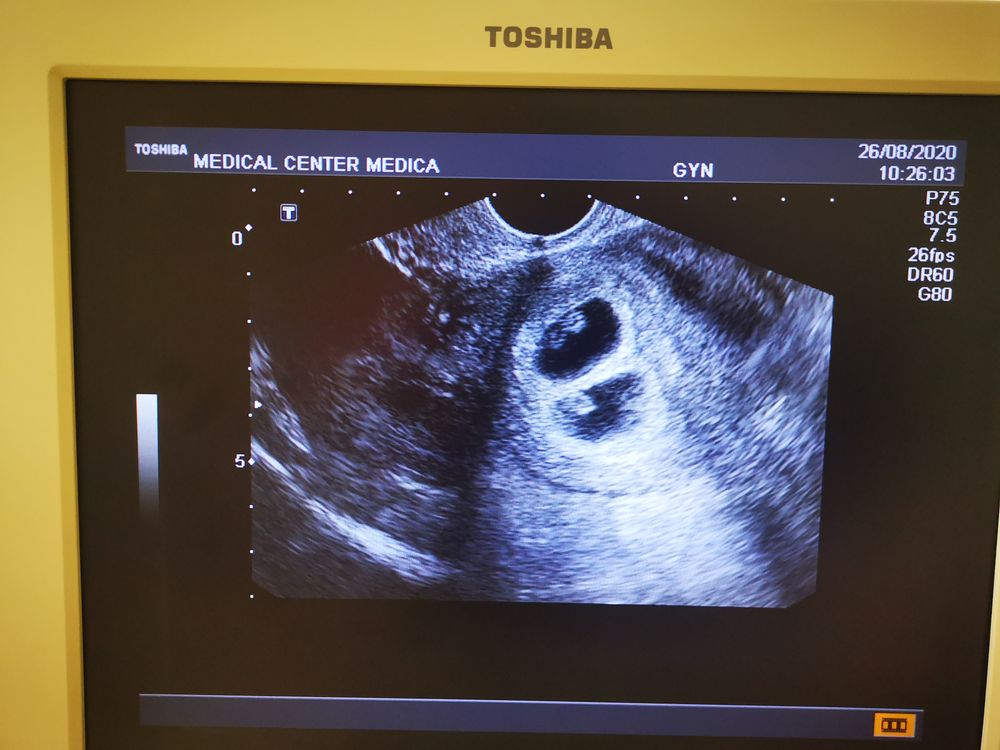

В общем, малыши растут, сердечко бъется в правильном ритме, показали у каждого сердцебиение! Это так мило😍😍😍